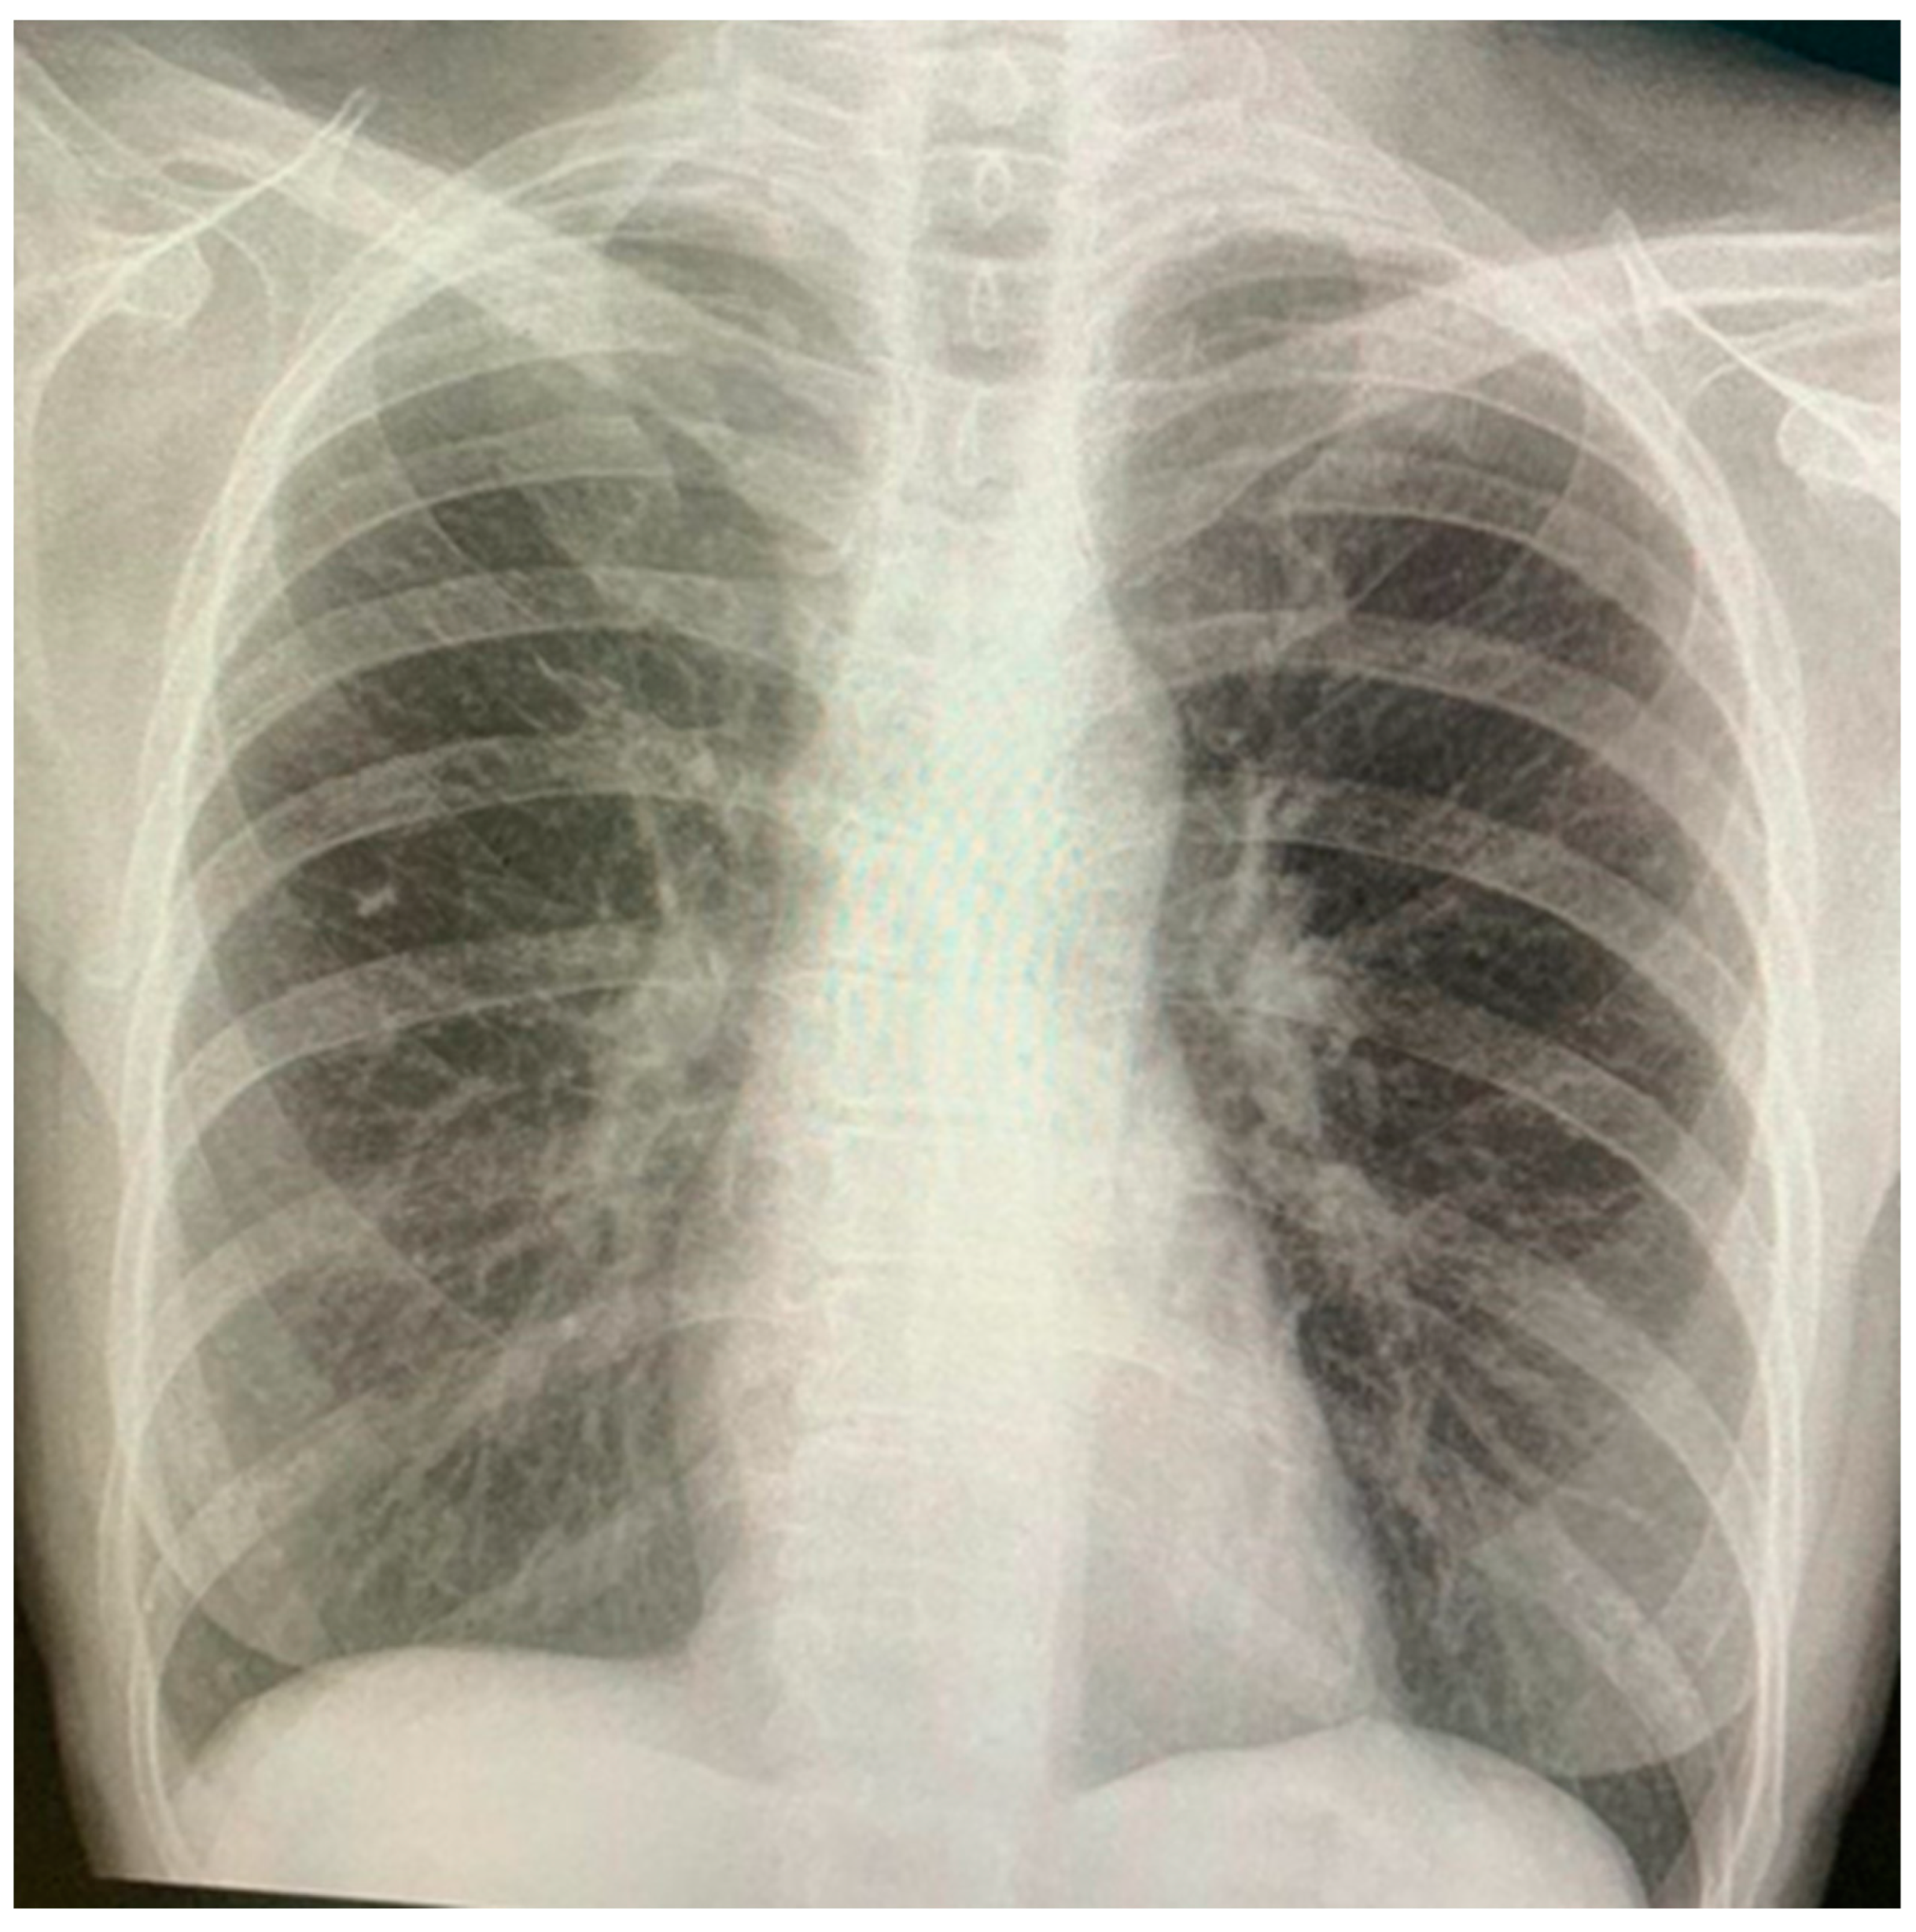

2.1. Diagnostic Imaging and Video-Assisted Thoracoscopic Surgery (VATS)

2.3. Treatment and Follow-Up